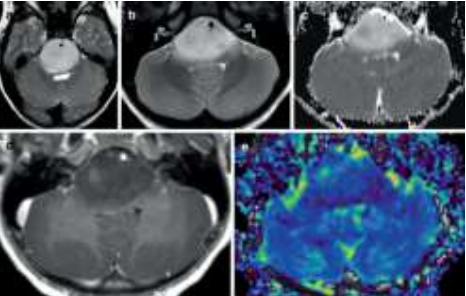

Criança de 7 anos, com histórico recente de diplopia por alteração da mobilidade ocular extrínseca foi encaminhada para realização de ressonância nuclear magnética de crânio em contexto de investigação diagnóstica, apresentando a seguinte imagem:

Baseado nas características epidemiológicas e os achados de seu exame de imagem, e considerando a classificação dos tumores do sistema nervoso central da OMS (2021), assinale a alternativa correta.